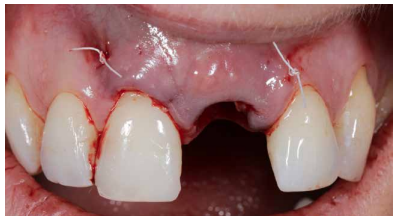

Caso clínico: Se presenta el caso de una paciente mujer de 32 años de edad, que acude por presentar una posible fractura radicular del incisivo central superior izquierdo (ICSI), acompañada de la aparición de un absceso periodontal en la región del fondo de vestíbulo de dicho diente. Tras llevar a cabo la exploración clínica y radiológica, se establece que el pronóstico del ICSI es desfavorable para llevar a cabo un tratamiento conservador del mismo. Tras la valoración de las características clínicas del caso presente, el plan de tratamiento se inclinó por la realización de la exodoncia del ICSI con la colocación simultánea de un IOI postextracción y la carga inmediata con una prótesis provisional del mismo.

Clinical case: We present the case of a 32-year-old female patient who presented with a possible root fracture of the upper left central incisor (ULCI), accompanied by the appearance of a periodontal abscess in the region of the bottom of the vestibule of said tooth. After carrying out the clinical and radiological examination, it is established that the ULCI prognosis is unfavourable for carrying out conservative treatment of the tooth. After assessing the clinical characteristics of the present case, the chosen treatment plan was to extract the ULCI with the simultaneous placement of a post-extraction osseointegrated implant (OII) and immediate loading of a provisional prosthesis on the implant.

Conclusiones: La rehabilitación sobre implantes en situaciones de pérdida dental en el sector anterior estético y en especial, en pacientes jóvenes, requiere un plan de tratamiento multidisciplinar en cuanto a la extracción del diente y colocación del IOI en la posición tridimensional correcta, existiendo diferentes aspectos a tener en cuenta para ello, especialmente el remanente óseo residual, la posición del margen gingival, así como la preservación y acondicionamiento de los tejidos duros y blandos periimplantarios mediante injertos y un manejo correcto de una prótesis provisional hasta conseguir un perfil de emergencia y contorno gingival ideal antes de la corona definitiva

Conclusions: Rehabilitation on implants in situations of tooth loss in the aesthetic anterior sector, especially in young patients, requires a multidisciplinary treatment plan in relation to tooth extraction and placement of the OII in the correct three-dimensional position. There are various aspects to be taken into account, particularly the residual remaining bone, the position of the gingival margin, as well as the preservation and conditioning of the peri-implant hard and soft tissues by means of grafts and proper handling of a provisional prosthesis until an ideal emergence profile and gingival contour is achieved before the final crown.

Así mismo, se han establecido diferentes protocolos para el manejo del sector estético anterosuperior, que se suman al acto de la colocación inmediata del implante y la corona provisional, donde se incluyen la colocación de un material no reabsorbible entre el IOI y la cortical vestibular para minimizar el posible colapso, así como el manejo de los tejidos blandos periimplantarios8-11.